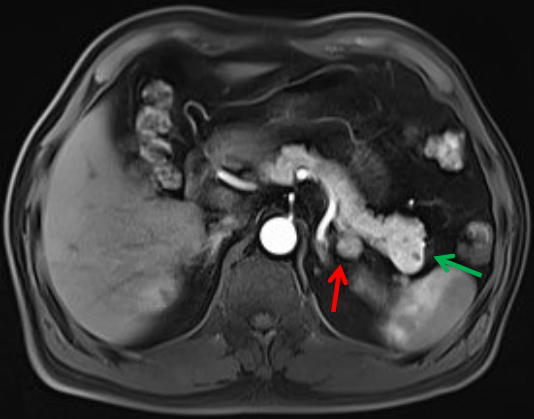

胰腺尾部肿瘤(绿色箭头)

和肾上腺肿瘤(红色箭头)